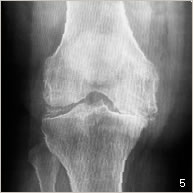

L’arthrose est l’usure du cartilage présent au niveau des surfaces de glissement. Cette usure s’accompagne aussi de remaniements de l’os du fémur, du tibia et de la rotule (figures 2 et 5). Ces modifications occasionnent des douleurs au niveau du genou ainsi qu’un enraidissement et une difficulté à la marche nécessitant l’utilisation importante d’anti-inflammatoires, d’anti-douleurs et parfois même d’une canne.